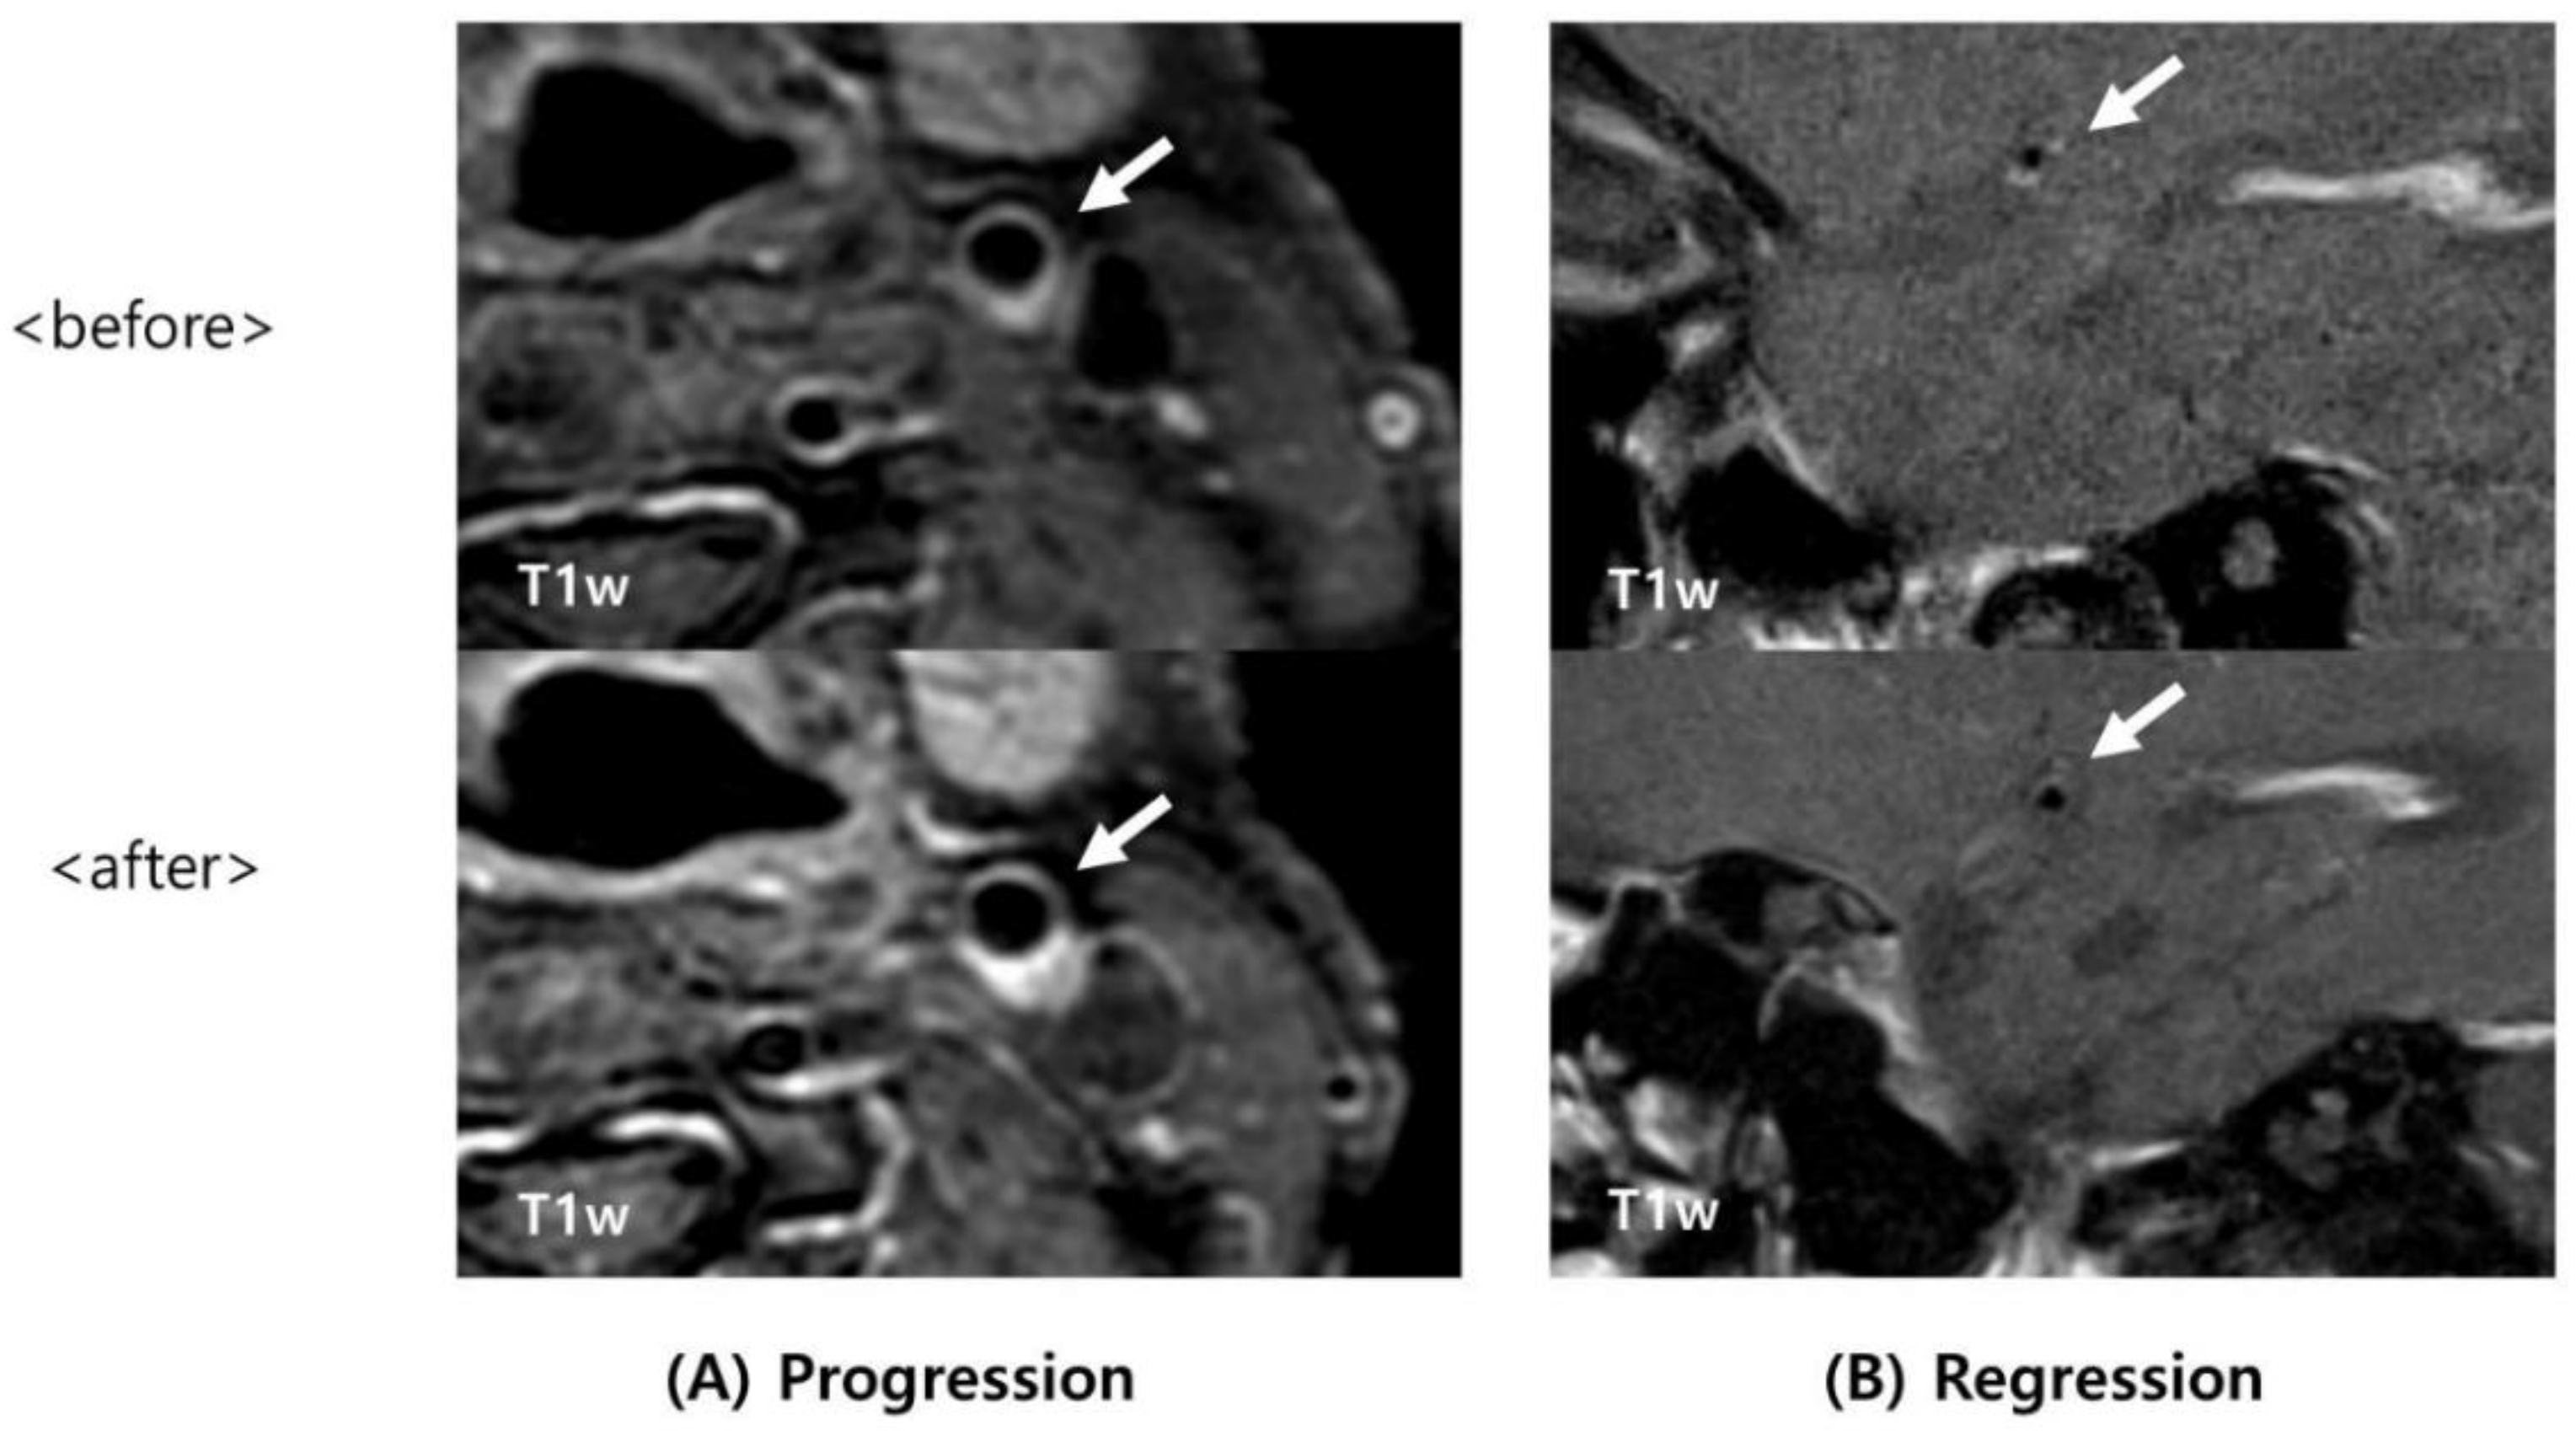

2.4. Image Analysis

3. Results

4. Discussion